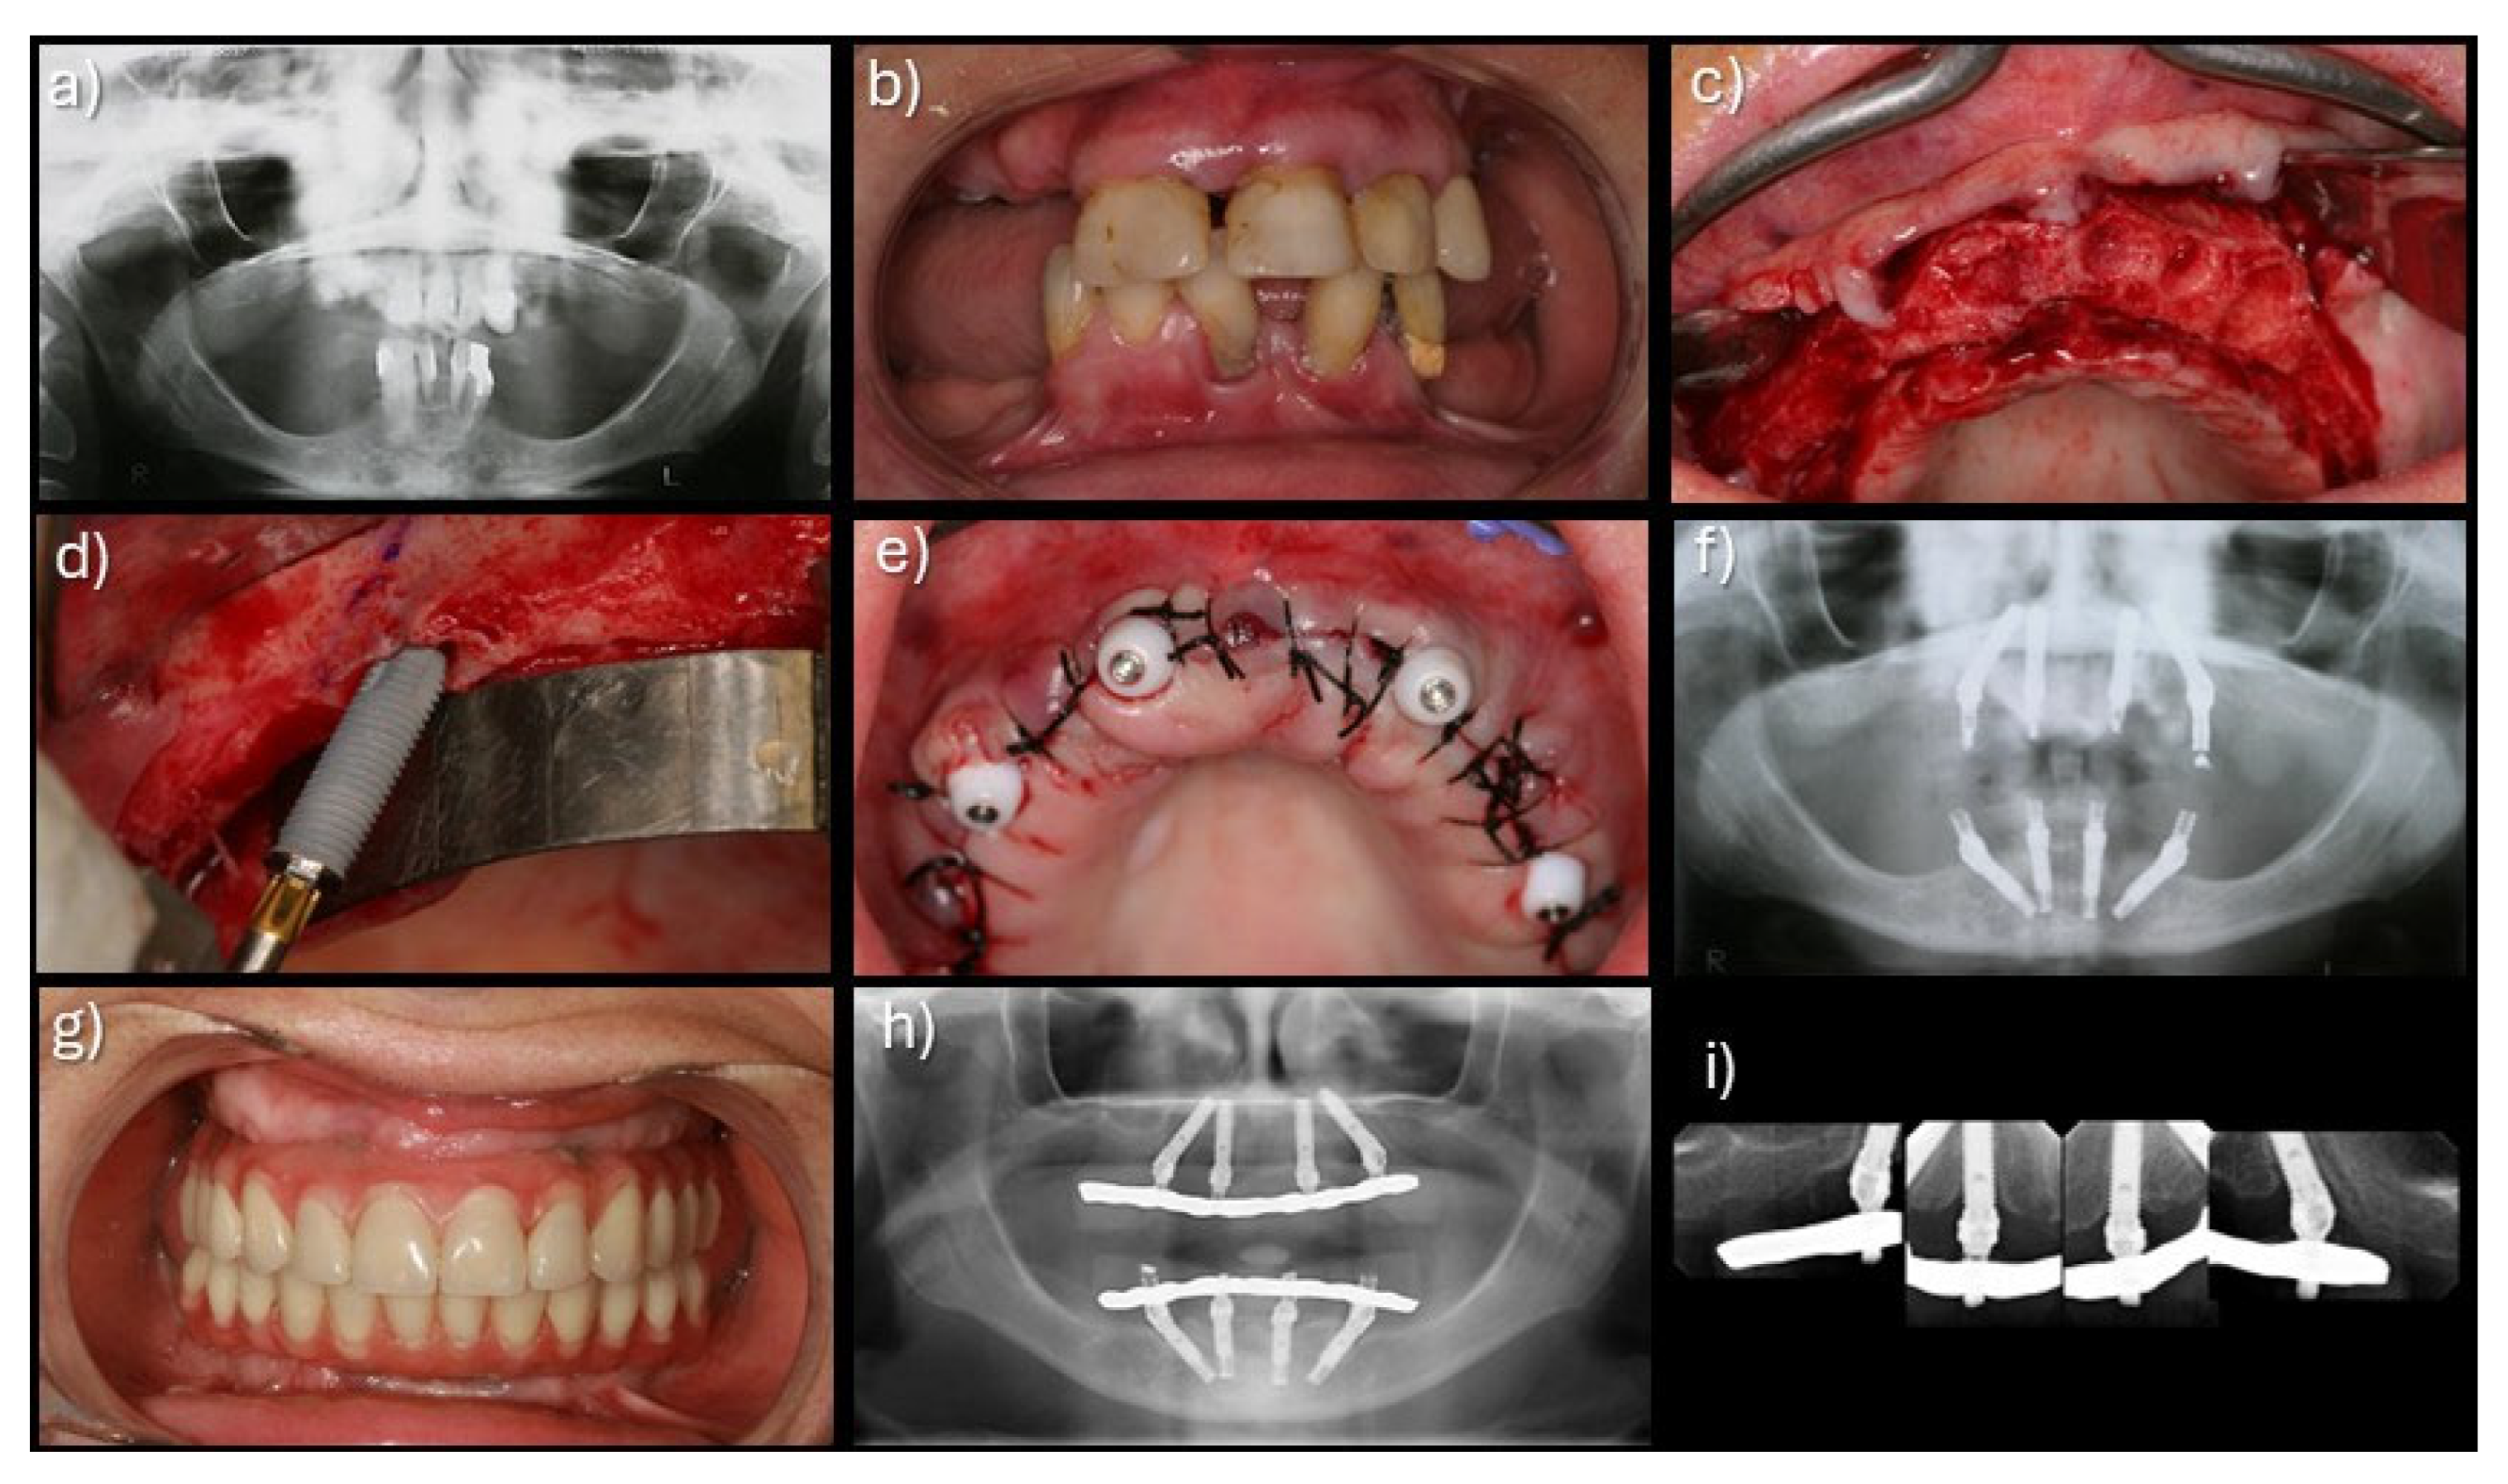

Patients were instructed to follow a soft-food diet during the initial postoperative period and were enrolled in a standardized maintenance program including oral hygiene instructions [13]. The recall regimen was set at 10 days; 2, 4, and 6 months; 1 year; and every 6 months thereafter, and included prosthesis removal, diagnosis, professional prophylaxis, and reinforcement of oral hygiene measures. A clinical case with very long-term follow-up is illustrated in Figure 1.

Figure 1. Clinical case of an immediate implant-supported full-arch maxillary rehabilitation using 4 implants and posterior implant tilting, from implant insertion to 20 years: (a) pre-treatment orthopantomography; (b) pre-treatment intra-oral view; (c) per-operative intra-oral view after teeth extraction and bone regularization; (d) per-operative intra-oral view of the insertion of the tilted posterior implant anterior to the maxillary sinus; (e) per-operative intra-oral view after implant insertion and suturing; (f) orthopantomography on the day of surgery with immediate prosthesis in place achieving immediate function; (g) intra-oral view of the definitive prostheses in place; (h) orthopantomography with the definitive prostheses in place; (i) periapical radiographs of the maxillary rehabilitation at 20 years of follow-up.